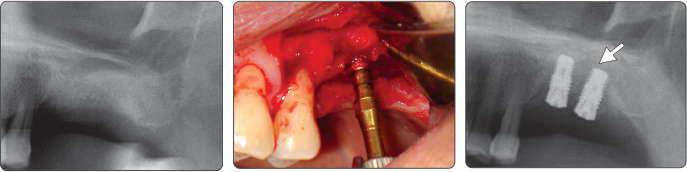

2. Sinus Lift Elevación de seno (Implante Ø5.0)

▶ Immediate Implantation and Sinus Lift Technique with Tap Drill (Ø5.0 Fixture)